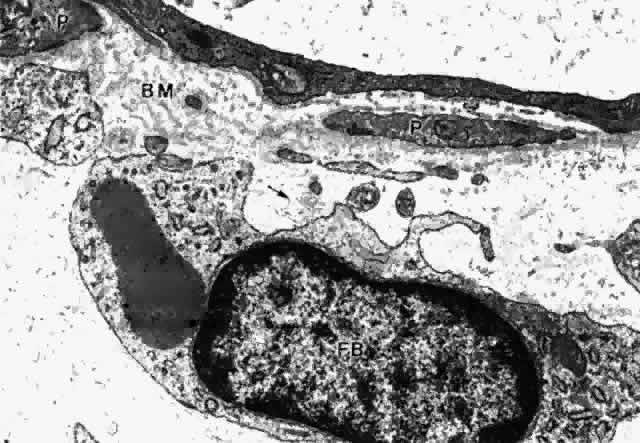

CILIARY BODY STROMA

The stroma of the ciliary body contains all the usual components of extracellular matrix including collagens, elastic system fibers, and small matrix molecules such as proteoglycans. The cellular components are melanocytes, fibroblasts, blood vessels, and nerves, besides the large quantity of smooth muscle comprising the bulk of this tissue. In the first one and one-half decades the nonvascular connective tissue in the ciliary processes is scanty, resulting in the thin, underdeveloped appearance of the juvenile ciliary processes (Fig. 28A). Their vessels are primarily fenestrated capillaries and veins, forming plexi (see later section on blood supply). The subepithelial tissue in the processes and plicae becomes very much thickened by collagenous and hyaline material with aging (Fig. 28B and C), extending down to the ciliary muscle itself. In the deeper stroma, capillaries are usually not fenestrated and show intermittent pericytes outside the endothelial cell layer, surrounded by basement membrane that merges with that of the endothelial cells (Fig. 29). The ciliary processes are essentially vascular structures and do not contain extensions of the ciliary muscle, so the muscle has the same thickness under the processes as under the ciliary valleys (Fig. 30).

Fig. 29. Intermittent pericyte (P) coverage and lack of fenestrae in the endothelial cell wall characterize capillaries of the deeper stroma in the pars plicata. Basement membrane (BM) is multilayered. Fibroblast (FB) has active rough endoplasmic reticulum and a large cisterna with granular material. A small clump of elastic system microfibrils is seen at its upper edge (arrow). (X 20,900)